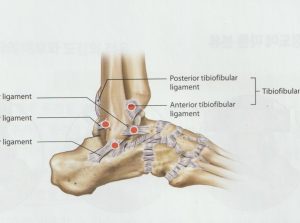

발목관절 염좌 안녕하세요, 고래한의원 박대명 원장입니다. 오늘은 일상에서 흔히 “발목을 삐었어요”라고 말하는 상황과 관련된 발목 염좌에 대해 설명드리겠습니다. 발목 관절은 여러 개의 뼈가 맞물려 구성된 구조로, 상당히 정교하게 이루어져 있습니다....

안양 고래한의원 - 발목관절 염좌001